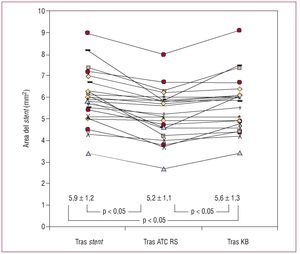

En todos los pacientes se consiguió el éxito inicial del procedimiento. En 1 (4%) caso hubo que implantar un segundo stent en el RS por obtener un resultado subóptimo tras la dilatación. En las tablas 3 y 4 se resumen los hallazgos ultrasónicos en cada estado de los distintos segmentos analizados. En el segmento proximal del stent y a nivel de la salida del RS se produce un incremento significativo del área y una pérdida de la geometría del stent tras el KB (figs. 2 y 3). En el segmento inmediato a la salida del RS se produce cierto grado de deformidad y pérdida de área tras dilatar el RS. Tras el KB se produce un leve incremento del área, aunque no llegaba a recuperarse hasta los valores basales a pesar de que el balón del stent era de mayor diámetro que el del RS y que el inflado se hacía a más atmósferas (12-14 AT en el VP, 6-8 AT en el RS). La figura 4 ilustra los cambios individuales en el área del stent tras cada estado en este segmento. En nuestro estudio no se encontró correlación alguna entre la angulación del RS y el grado de deformidad producido en el bajo rombo tras dilatar aisladamente el RS. En el stent distal, no se objetivaron diferencias significativas en ninguno de los estados.

Fig. 4. La gráfica muestra los cambios individuales producidos en el área del stent a nivel del bajo rombo tras cada intervención. En la parte inferior de la gráfica se reflejan la media ± desviación estándar y la significación de las diferencias entre las medias. KB: kissing balloon; RS: rama secundaria.

Si analizamos el segmento inmediato a la salida del RS, observamos que se produce una deformación en la geometría del stent (el IS pasa de 0,82 a 0,74; p < 0,01) y una discreta pérdida del área a dicho nivel, pasando de 5,9 ± 1,2 a 5,23 ± 1,1 mm2 (p < 0,05), lo que supone una pérdida del 12% del área del stent. Sin embargo, el espectro de deformación del stent en el bajo rombo es amplio, y varía desde casos en los que no se produce modificación alguna (fig. 2) a otros en que la deformación es más marcada (fig. 3). Quizá el diámetro del balón utilizado para dilatar el RS, el grado de angulación o la pata metálica por la que pasan la guía y el balón podrían modificar el grado de deformación del bajo rombo, y sería interesante determinar los posibles factores que influyen en dicha deformación en estudios ulteriores. En nuestro estudio no se encontró correlación alguna entre la angulación del RS y el grado de deformación en el bajo rombo (r = 0,32; p = 0,1). Además se dividieron los casos en ángulos > 60° y < 60°, y analizamos la pérdida de área del stent tras dilatar el RS y el grado de recuperación tras el KB; no se encontraron diferencias entre los dos grupos. En 6 (26%) casos, el área del stent osciló entre 4 y 5 mm2 y sólo 3 (14%) quedaron con un área luminal < 4 mm2, cifra por encima de la cual se considera poco probable que se produzcan defectos de perfusión14-18.

Tras el KB, la geometría del stent no queda restaurada (IS tras dilatar RS, 0,74; IS tras KB, 0,77; p = 0,168) y no se produce una recuperación completa del área del stent (área basal del bajo rombo, 5,9 mm2; área del bajo rombo tras el KB, 5,6 mm2; p < 0,05), ganando un 7% del área perdida tras dilatar el RS. Por lo tanto, a pesar de que el balón del VP era de mayor diámetro que el usado en el RS y que la presión aplicada durante el KB fue mayor en el balón del stent, no se consigue restaurar en su totalidad la deformación producida en el bajo rombo. En nuestro estudio, donde menos expansión se consiguió en relación con los otros segmentos estudiados es tras la salida del RS. Si analizamos las lesiones angiográficamente antes del tratamiento, vemos que 20 (87%) pacientes tenían enfermedad distal a la bifurcación, lo que puede explicar este fenómeno. En cuanto al stent distal, como era de esperar, no se produjo ninguna modificación con respecto a su situación basal, ya que a ese nivel no hubo ninguna manipulación adicional durante las distintas fases del proceso.